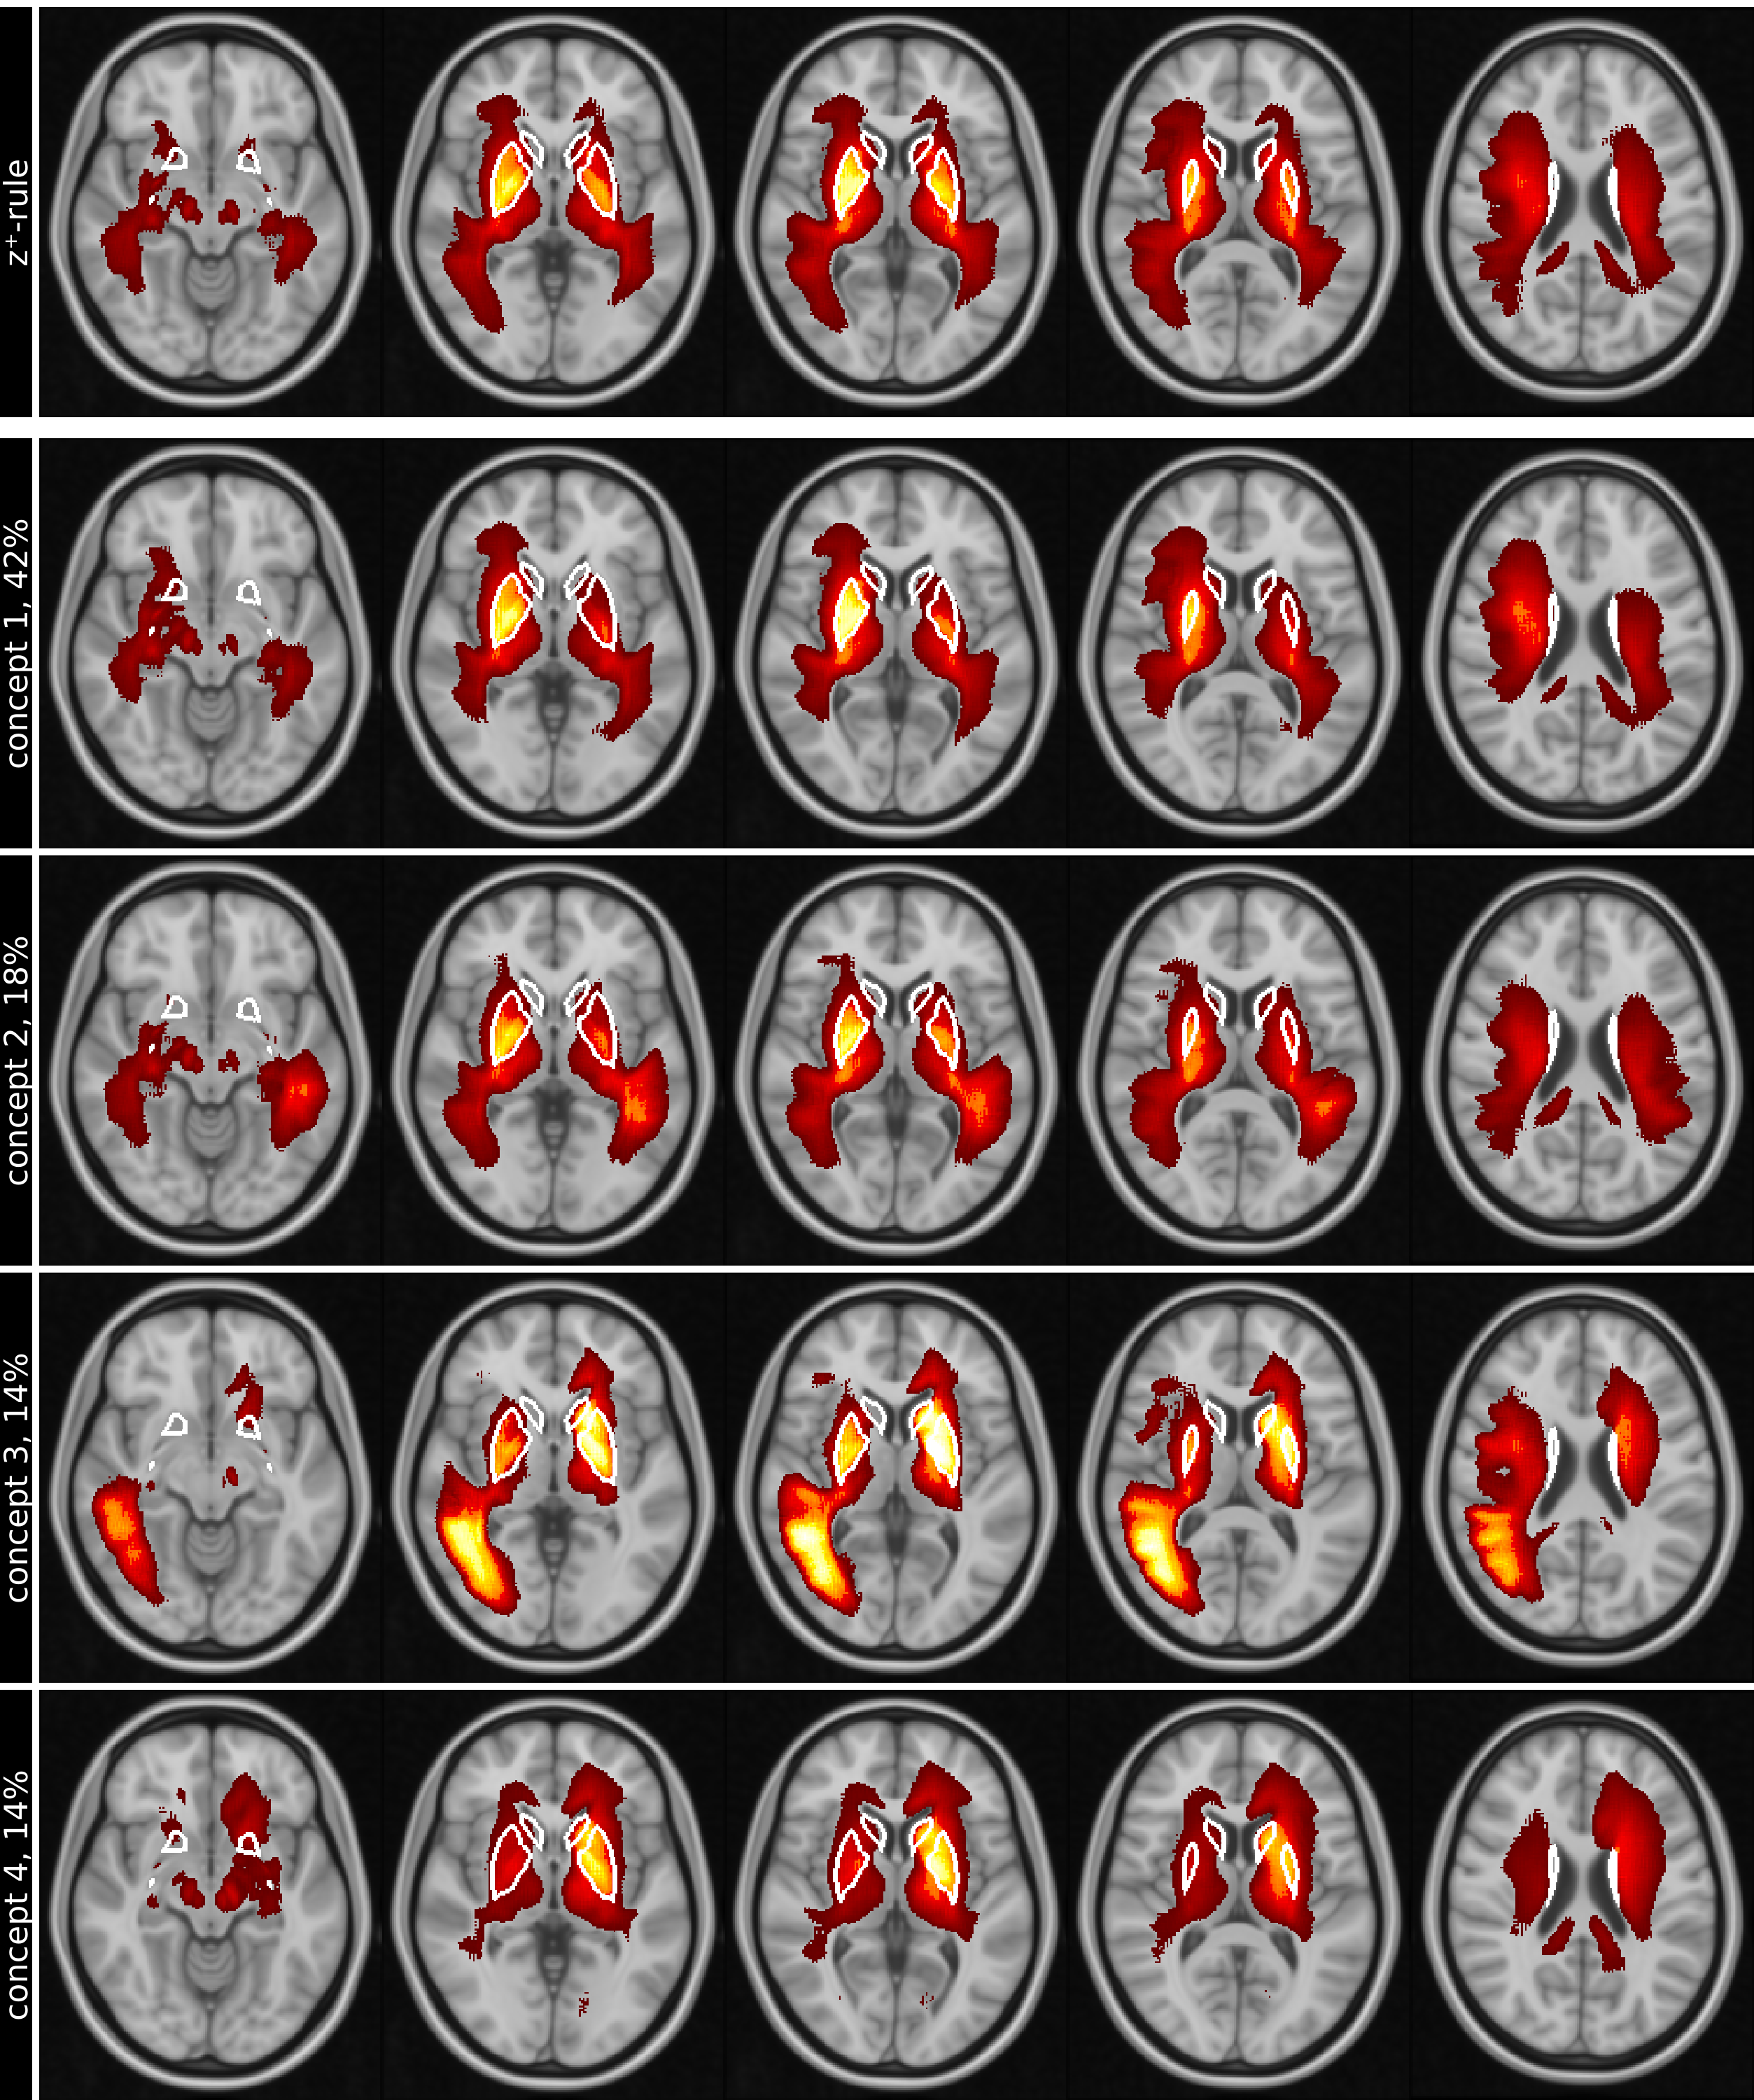

Figure  3 shows the five top ranked test images for each concept on the same transversal slice, while figures 4 and 5 show the mean concept maps for NC and AD on five transversal slices.

Refer to caption

Figure 5: Row (1) shows the conventional mean global heat maps created for AD using LRP-z+superscript𝑧z^{+}-rule for 5 slices (columns), overlaid on the MNI152 standard-brain 1mm template. In comparison, rows (2) to (5) show the 4 most important concepts on the same slices, ranked by their relative importance (percentage next to name) for the classification results. Positive relevance, shown as red-yellow, highlight regions in concepts with higher attributions. White lines in slices outline the basal ganglia. Images are shown in standard-radiological view, causing the left and right side of the brain to be flipped.